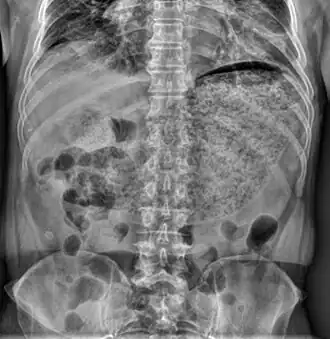

Le temps de vidange gastrique peut être estimé par une scintigraphie : un traceur radioactif est ingéré en même temps qu'un repas et une imagerie abdominale est faite à plusieurs temps, jusqu'à quatre heures après[4]. Une variante consiste à déterminer le temps où un traceur ingéré arrive dans l'air expiré[5]. Il existe également des capsules électroniques qui peuvent être avalées et enregistrer différents paramètres[6].